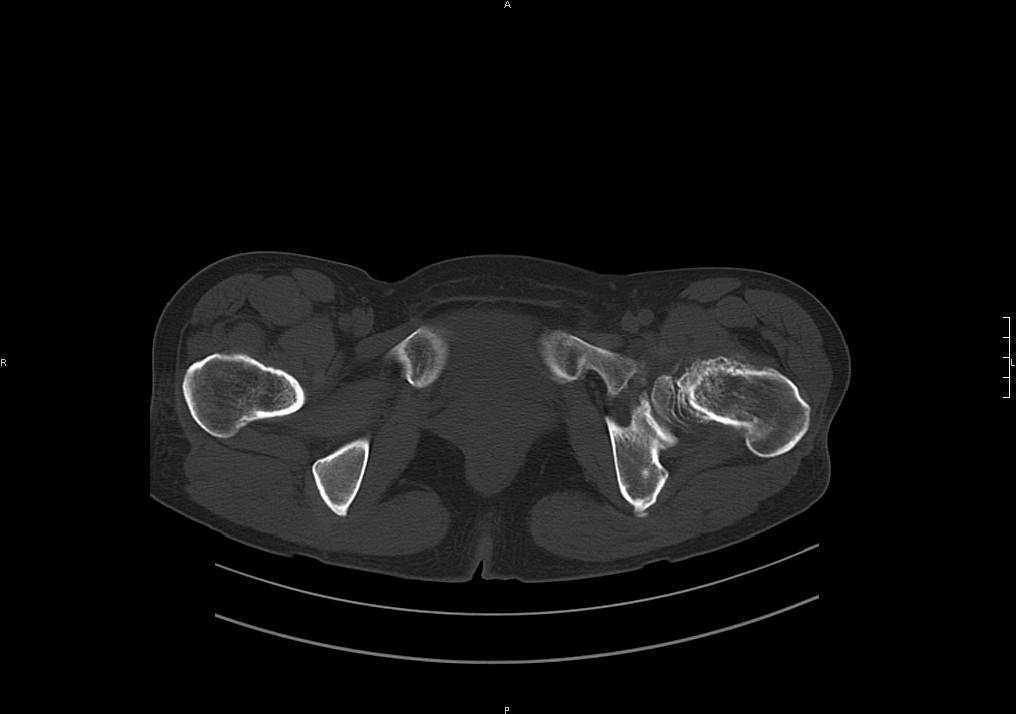

标题: CT19780左髋关节疼痛伴跛行1年,加重1个月。无菌性坏死? [打印本页]

标题: CT19780左髋关节疼痛伴跛行1年,加重1个月。无菌性坏死?

退行性骨关节病可能性大。

滑膜增厚钙化,关节鼠及滑囊积液,髋臼增生。考虑骨性关节病

考虑左髋关节退行性骨关节病;建议必要时行mri检查排除左侧股骨头缺血性坏死。

退行性骨关节病

考虑左髋关节退行性骨关节病